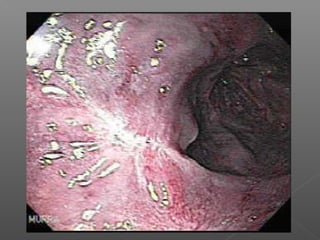

Pronóstico: Clasificación de Forrest

 I a: hemorragia en chorro 90%

 I b: hemorragia por escurrimiento 10%

 II: estigmas de sangrado reciente:

 II a: vaso visible 50%

 II b: coagulo adherente 33%

 II c: base necrótica 7%

 III: Úlcera limpia 3%

Pronóstico (sangrado no variceal)

Clasificación de Forrest (riesgo de resangrado)

Forrest Ia Forrest Ib Forrest IIa

Forrest IIb Forrest IIc Forrest III

Laine L New England Journal of Medicine 1994

67 a 95 % 25 a 55 %

15 a 30 % 4 a 7 % 0 a 5 %

67 a 95 %